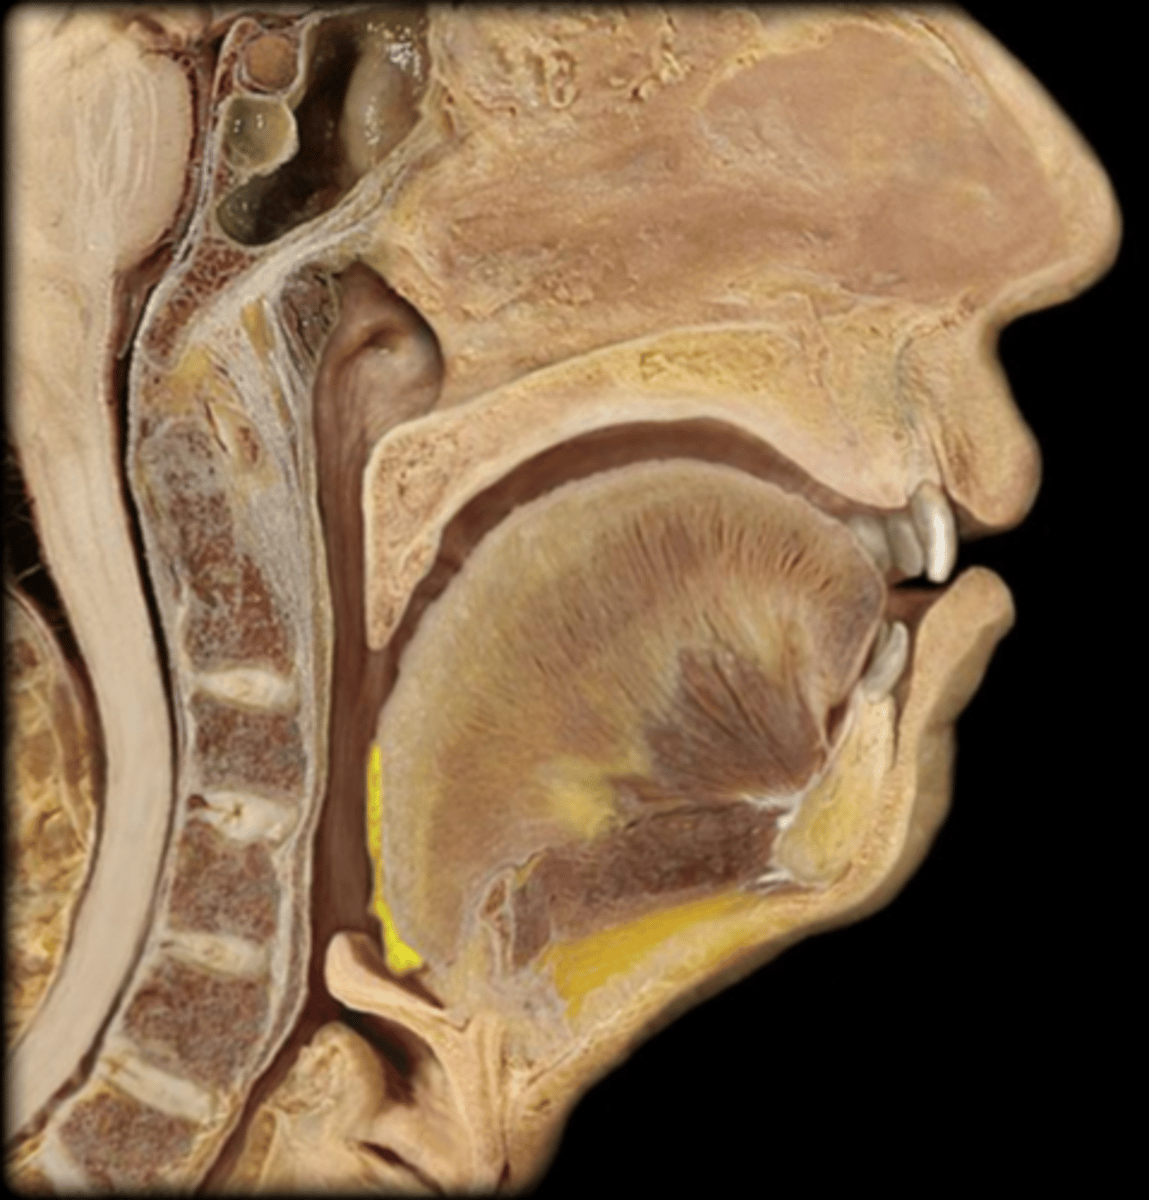

Tongue

Lingual Tonsil

Palatine Tonsil

Esophagus

Epiglottis